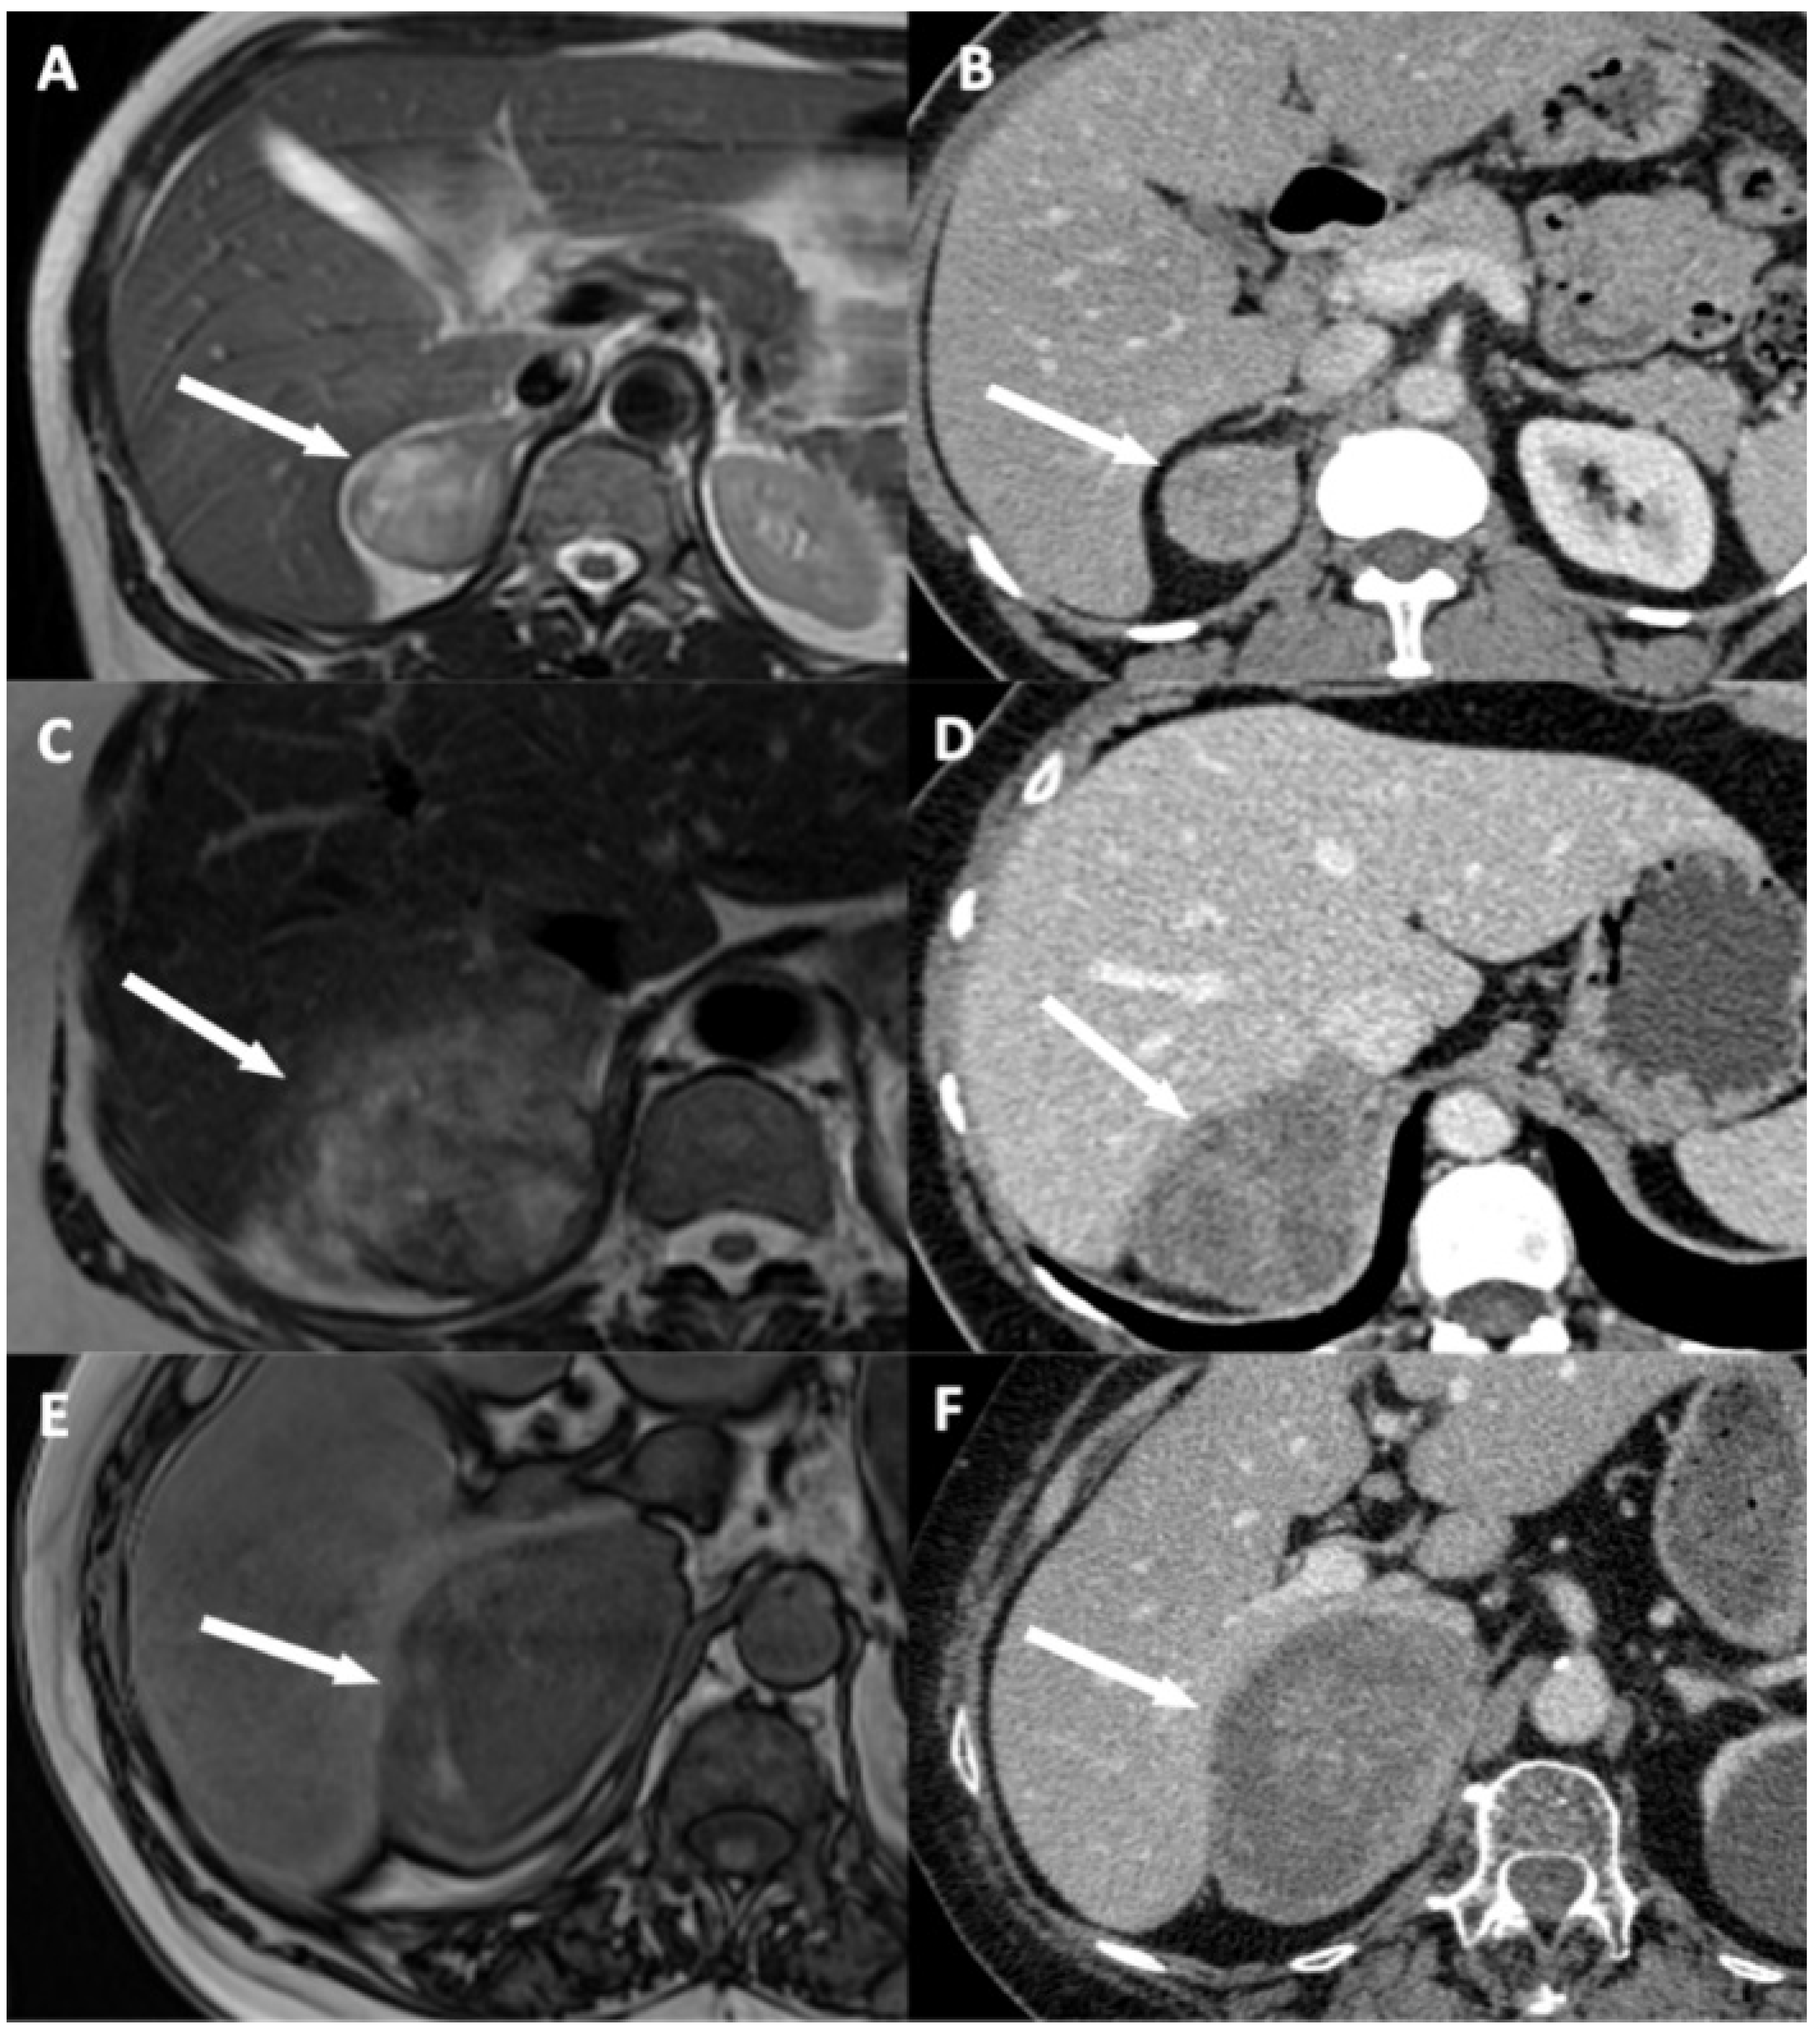

3.3. Qualitative Findings

| Disappearance of fat border between ACC and liver | Portal phase CT T2 HASTE MRI (**) | Fat border between ACC and liver non-measurable (<1 mm) |

| ACC contour disruption | Portal phase CT Portal phase MRI | Measurable adrenal capsular defect without any enhancement |

| Focal ACC bulge | Portal phase CT Portal phase MRI | Focal and abrupt irregularity of ACC shape |

| ACC inclusion by hepatic parenchyma > 180° | Portal phase CT Portal phase MRI | ACC surrounded by the liver parenchyma over its half-circumference |